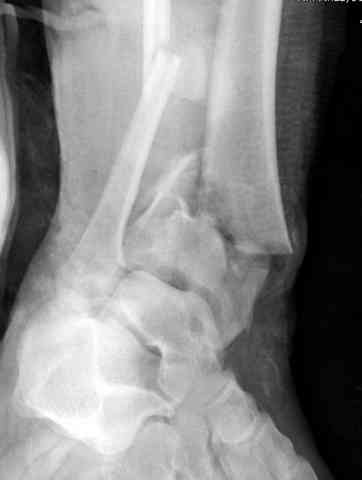

Открыто или закрыто - это уже зависит от опыта и

наличия материала. Минимальным аппаратом Илизарова или одним из Contoured Medial или Antero-Lateral Locking Plate из лимитирванного доступа не имеет значения, но самое главное необходимо добиться репозиции сустава.

Первичная пластина или интрамедуллярный фиксатор на малоберцовую зависит от характера перелома, косые и многооскольчатые пластинами, а поперечных можно интрамедуллярными фиксаторами. Восстановленная длина малоберцовой служит ориентиром и помогает определению высоты большеберцовой во время восстановления.

Переломы пилона сопровождаются ударом со сминанием в метафизарной части большеберцовой, то есть со значительной потерей костного объема.

При репозиции суставных поверхностей образуются полости в метафизарных отделах, без заполнения их

структуральными элементами невозможно предохраниться от посттравматической деформации. Латеральная колонна удерживается малоберцовой поэтому голень деформируется в варус.

Аутокость является самым надежным материалом, но при желании можно применить синтетический заполнитель Osteoset Pallets - структуральный материал, по аннотации материал через определенное время интегрируется в кость.

Здесь выставлена пара случаев перелома пилона, оба

случая леченные этапным наружным фиксатором.

Второй случай фиксирован аппаратом Илизарова.